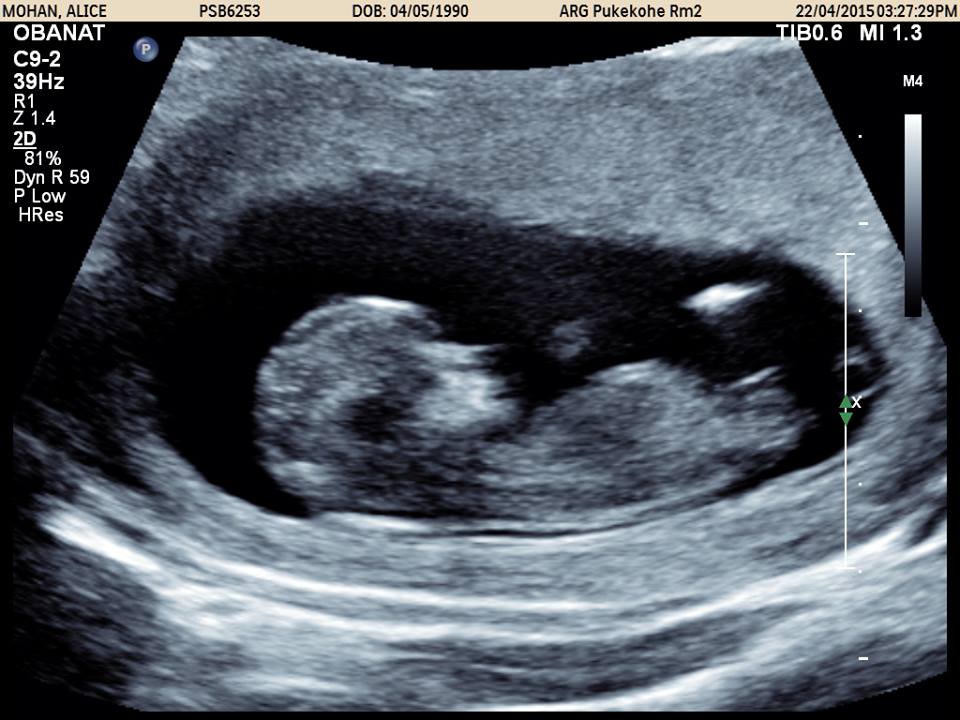

The nub is long and flat, but looks like it might be a bit on the rise. So I'm saying 70/30 for girl.

Girl but may rise. GL!!

bit early for me but tentative girl gues